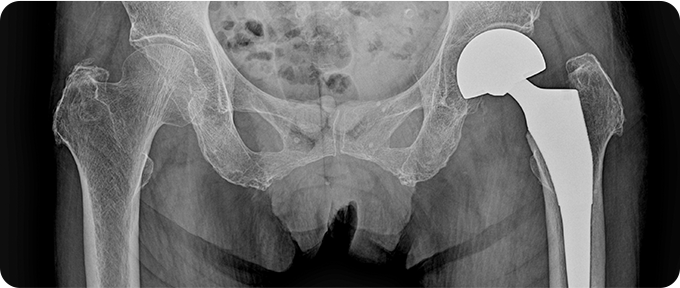

인공관절 수술

고관절 골절의 인공관절 수술은 손상된 관절을 제거하고 인공 관절로 대체하는 치료 방법입니다. 주로 심각한 골절이나 재건이 어려운 경우 시행됩니다. 수술 후 관절의 기능을 회복하고 통증을 줄이는 데 효과적이며, 재활 치료로 안정성과 가동성을 향상시킵니다. 환자의 상태에 따라 맞춤형 수술 계획이 필요합니다.